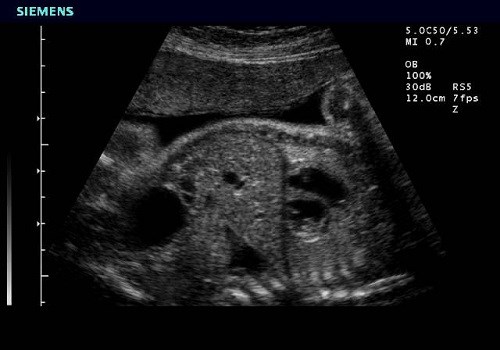

УЗИ (другие названия – «эхография», «сонография») основано на физических особенностях воздействия ультразвуковых волн медицинского оборудования с частотой 1,5-29 МГц на ткани различной плотности. Сопротивление отражает, преломляет, рассеивает звуковые колебания или полностью поглощает. В результате на приемном устройстве проявляется изображение морфологической структуры органа (контуров и внутренних структур). Наблюдение в динамике позволяет зарегистрировать функциональные изменения.

Современные ультрасонографические аппараты выводят на монитор цветную картину изучаемой зоны тела, наиболее информативны 3D или 4D- изображения. При обследовании желудочно-кишечного тракта врач описывает отклонения показателей внутренней структуры в зависимости от принятых анатомоультразвуковых норм. Обнаруженные признаки важны для первичной диагностики, подтверждения или исключения симптомов болезни.

Ультразвуковое исследование (УЗИ) кишечника является важным диагностическим методом, который позволяет врачам оценить состояние органов пищеварительной системы. Процедура проводится с помощью специального аппарата, который генерирует ультразвуковые волны. Эти волны проникают в ткани и отражаются от них, создавая изображение на экране. Врачи назначают УЗИ кишечника при подозрении на различные заболевания, такие как воспалительные процессы, опухоли или кишечные непроходимости.